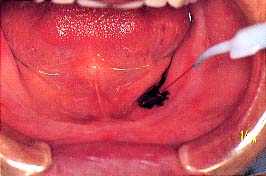

(4)義歯によるキズ

1.総義歯の部相当部に潰瘍形成が

認められる。

2.患部を充分乾燥後、歯科用のスミを

塗布する。そこにレーザーを照射

する。